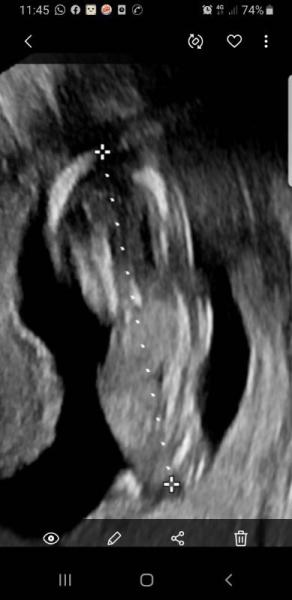

Hallo, Ich werd langsam wahnsinnig. Heute beim ultraschall sagte die fraienärztin alles zeitgerecht und super auf dem bild steht aber 13+3. Vielleicht hätte sie das kreuz schon am kopf höher setzen können. Und unten kann man es garnicht einschätzen wo das Kreuz hin kommt. Also 14+ 4 und 7.5 cm Wenn ich das vergrösser auf die 7.5 und mit dem lineal genau messe komme ich auf 8.

Bild zu 14+ 4 embyo zu klein - Forum für Juni - Mamis